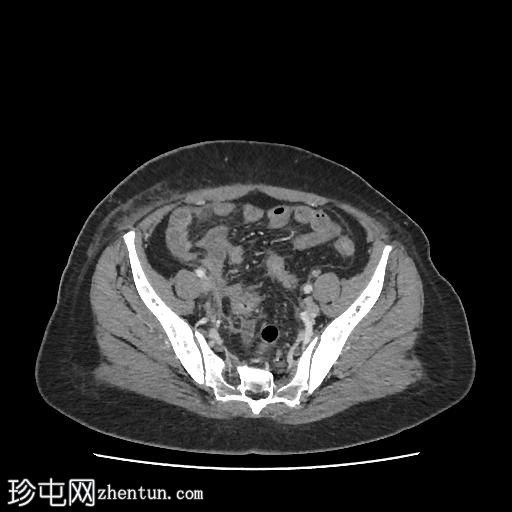

轴位肾盂排泄期

CT扫描显示:

左侧膀胱后外侧壁完全撕裂,造影剂外渗至盆腔

盆腔内可见少量积液

腹膜脂肪条索状改变,腹膜反折增厚强化,提示盆腔腹膜炎

腹腔镜

子宫切除术后医源性膀胱损伤伴盆腔腹膜炎的CT表现。